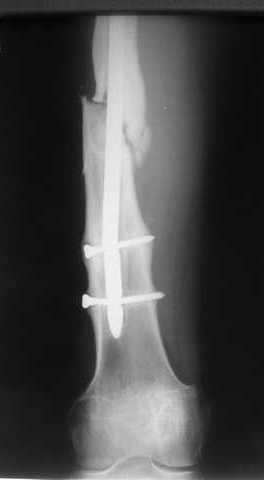

К нам больной поступил с признаками ложного сустава бедренной кости, перелома

штифта и дистального блокирующего винта (images 1,2,3).

27 марта выполнено удаление блокирующих винтов (сломанный винт пришлось высверливать цапфен-бором), сломанного штифта (дистальный фрагмент удален через канал, образованный разверткой из коленного сустава - image 4),

рассверливание костно-мозгового канала, реостеосинтез штифтом UFN (при проведении штифта в дистальном отломке мы использовали поляризующий винт, диаметр штифта 10 мм). После операции в связи гемартрозом дважды (на 1 и 3 сутки) выполняли пункцию коленного сустава. Сейчас признаков скопления жидкости в полости сустава нет. Послеоперационные рентгенограммы - images 5, 6, 7.